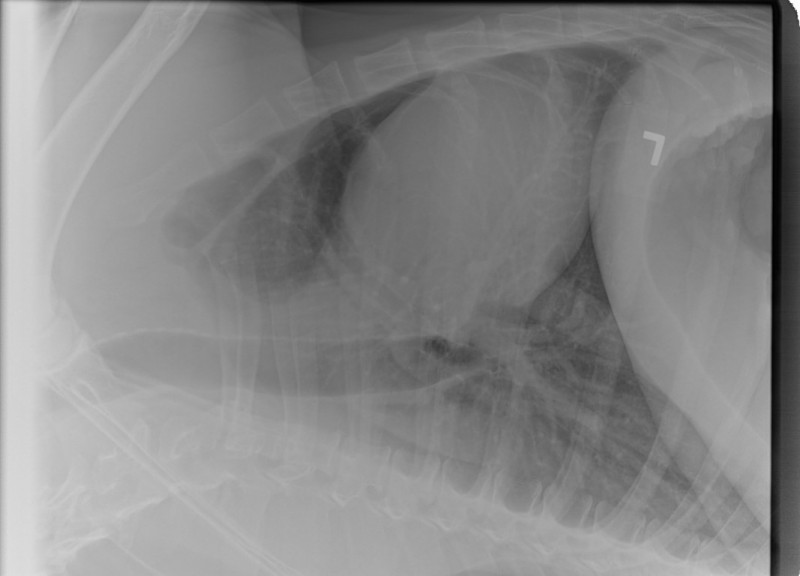

The Vet and I discussed x-days of her chest/lungs for her Vet was not comfortable with the looks of that remaining mass. frown emoticon Nor, with this sudden huge weight loss.

I was so worried gowning up to help with the x-Rays……

The good news is that her lungs, at this time have shown no signs of anything that has metastisized.

I have her x-Rays to post on her blog, photo’s of her masses and, one of a recovering sweet BHRR’s Ani from sedation. She also received a lovely mani/pedi!